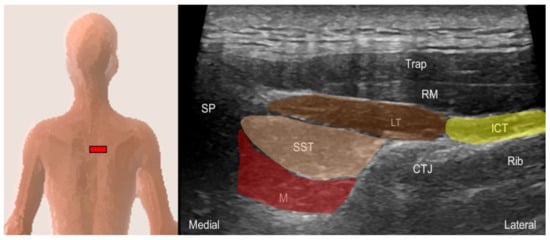

5.1.2. Sonographic Scanning